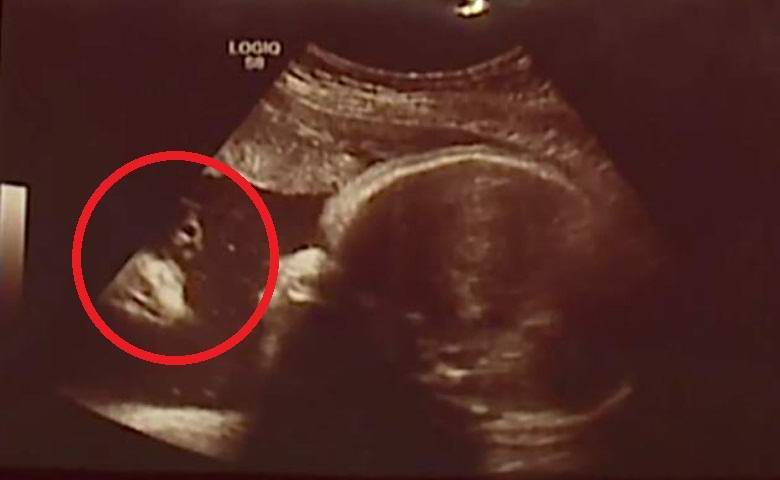

Házastársak az amerikai Chambersberg városból az államban Pennsylvania nem tudta elhinni a szemüket, amikor a képen volt, a méhben végzett ultrahangos vizsgálat során készültek megjelent az anyjuk, most született lánya, Briella egyértelmű vallási jel. A fénykép bal oldalán megjelent egy hosszú hajú, szakállas férfi alakja, köpenyben közvetlenül a magzat arcára nézve. Mint gondolnád, jövő a szülők azonnal úgy érezték, hogy ez Jézus Krisztus képe.

fénykép nyílt forrásokból